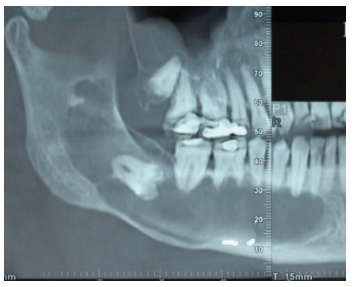

Acudió a servicio de cirugía oral, derivado por su odontólogo, un paciente varón de 65 años sin antecedentes médicos de interés, tras comprobar un importante crecimiento de una imagen radiotransparente respecto a última radiografía de hacía 5 años. El paciente no refirió sintomatología asociada. A la exploración extraoral no se apreció ningún tipo de deformidad ni afectación ganglionar. A la exploración intraoral pese a que se constató la integridad de las corticales, las cuales no estaban abombadas, sí que se pudo apreciar a la palpación un signo positivo de Dupuytren o de “Ping-Pong”. Además se constató una falta de afectación de los dientes del cuarto cuadrante que no presentaban movilidad y tenían una vitalidad positiva (Figura 1). Como complemento a la exploración clínica se solicitó un estudio mediante TAC, donde se apreció la extensión de una lesión radiotransparente que afectaba a rama y cuerpo mandibular derecho. (Figuras 2 y 3).